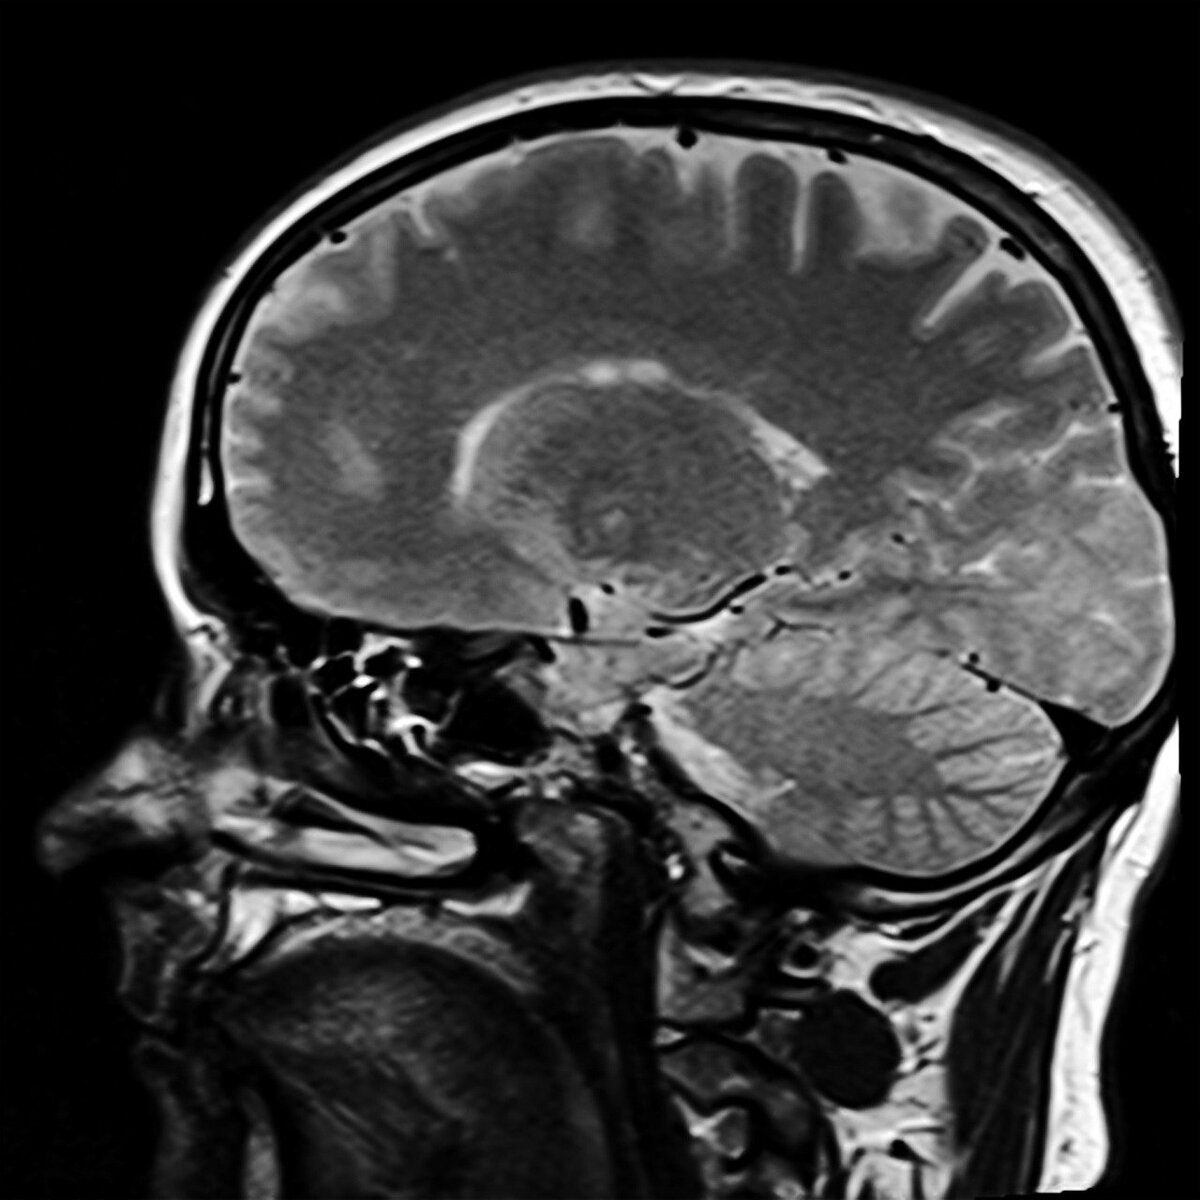

Низкий уровень определенного белка в передних участках мозга обнаружен у пациентов с шизофренией. Сотрудники Лондонского института медицинских наук изучили мозг 18 пациентов с шизофренией и, для сравнения, 18 здоровых людей. В мозг был введен маркер, который связывается с белком SV2A, находящимся в синапсах. С помощью томографии ученые впервые благодаря маркеру смоги тщательно рассмотреть определенные участки мозга и проанализировать работу нейронов. Было обнаружено, что у людей с диагнозом «шизофрения» уровень белка в передних участках мозга ниже, чем у здоровых. Эти отделы отвечают за планирование действий. Как известно, один из симптомов психического заболевания – неспособность планировать и запоминать свои действия. Таким образом, теперь у исследователей заболевания есть новые цели для разработки методов лечения, пишет «Вевбай».

Сотрудники Лондонского института медицинских наук изучили мозг 18 пациентов с шизофренией и, для сравнения, 18 здоровых людей. В мозг был введен маркер, который связывается с белком SV2A, находящимся в синапсах.

С помощью томографии ученые впервые благодаря маркеру смоги тщательно рассмотреть определенные участки мозга и проанализировать работу нейронов.

Было обнаружено, что у людей с диагнозом «шизофрения» уровень белка в передних участках мозга ниже, чем у здоровых. Эти отделы отвечают за планирование действий. Как известно, один из симптомов психического заболевания – неспособность планировать и запоминать свои действия.

Таким образом, теперь у исследователей заболевания есть новые цели для разработки методов лечения, пишет «Вевбай».